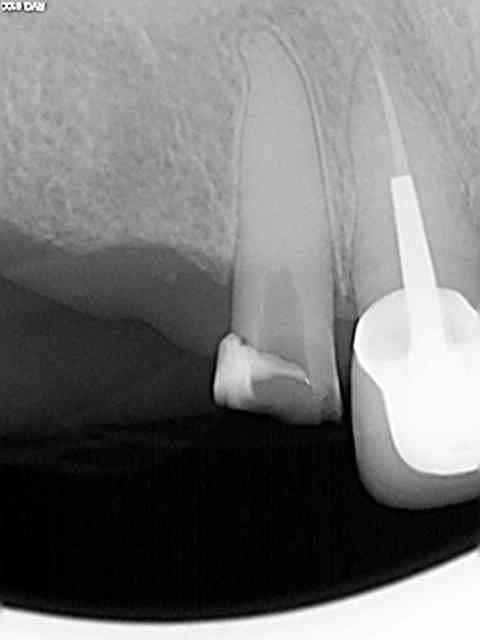

Exemple sur cette 12 tout à l'heure, 1h 30 de rdv terminé en 1h et encore j'ai un peu "tâtonné" pour trouver la pulpe. Toujours pas de cathétérisme manuel of course sinon j'y serais encore.)))))